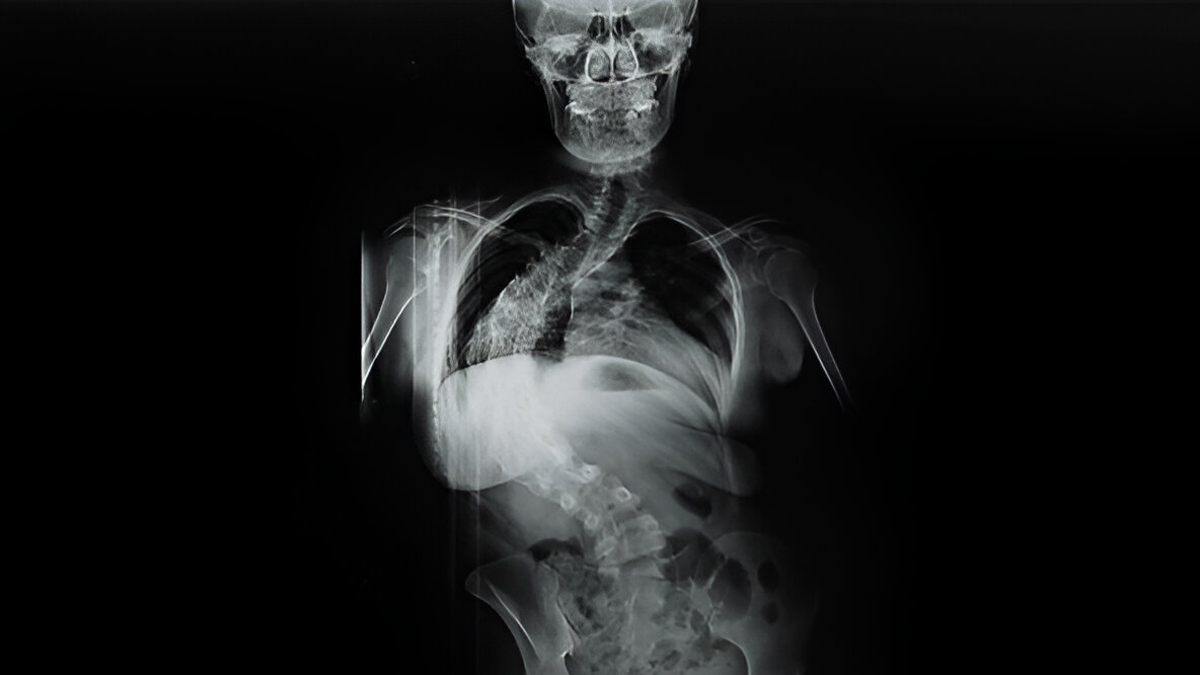

For a diagnosis of scoliosis, the spinal curvature must measure at least 10 degrees on an X-ray taken from the front (coronal plane). While most cases are mild, only about 0.1% of children develop more severe curves—over 40 degrees—which are more likely to require surgery. Recognising and monitoring the condition early can help prevent it from progressing to the point where invasive treatment becomes necessary.

The condition is usually diagnosed through a physical exam followed by imaging tests. “Doctors usually start by looking at the child’s back and posture. They may ask the child to bend forward to see if one side of the ribs sticks out more; this is called the Adam’s Forward Bend Test,” says Dr Hari. “If scoliosis is suspected, an X-ray is taken to see the spine clearly. The curve of the spine is measured using something called the Cobb angle. If the angle is more than 10 degrees, it’s considered scoliosis. This helps doctors decide how serious the curve is and what kind of treatment is needed. Early diagnosis means better chances of managing the condition well.”